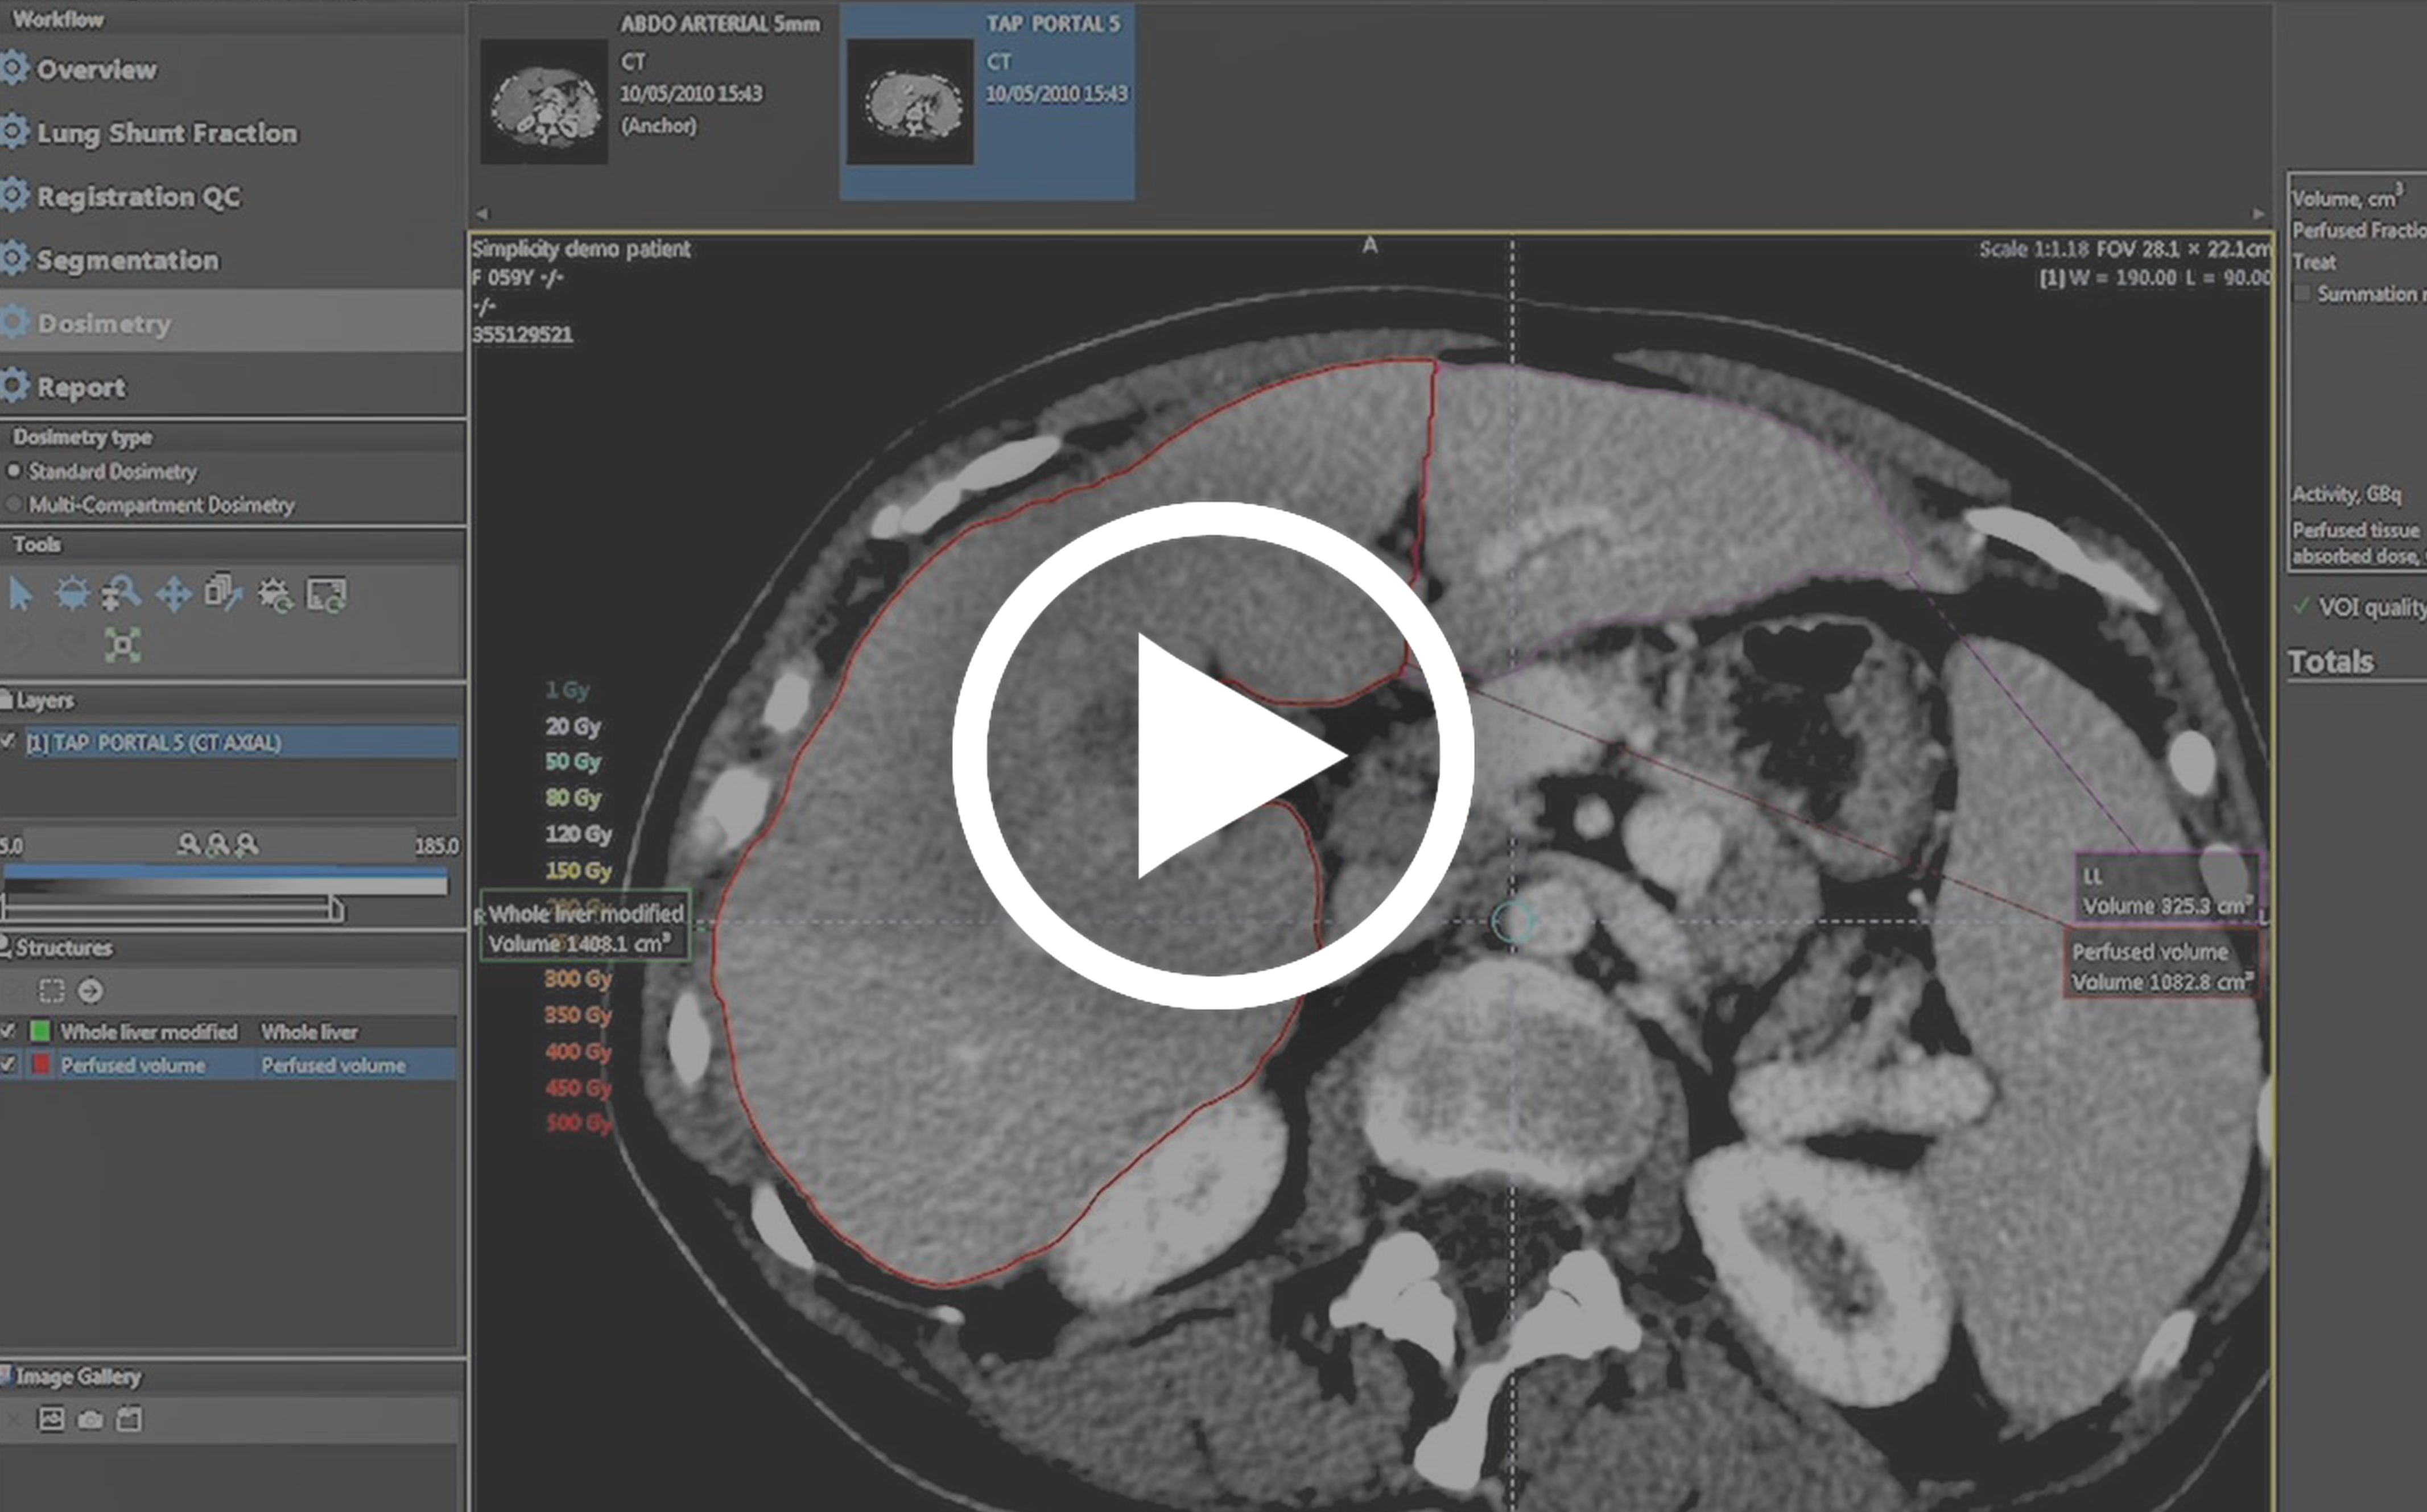

Simplicit90YTM is a customised, easy-to-use dosimetry software developed for accelerating treatment planning and improving 90Y Glass Microspheres Selective Internal Radiation Therapy (SIRT) workflow.

The software enables to quickly embrace Personalised Dosimetry in your clinical practice with dedicated tools and features thereby reducing inter-user variability and improving dosimetric consistency.

Simplicit90Y™ can be used to interactively tailor the absorbed dose per perfused volume by adjusting the injected activity. The software tools can be customised to a patient’s specific tumour presentation and anatomy.

High performance rigid and deformable

image registration